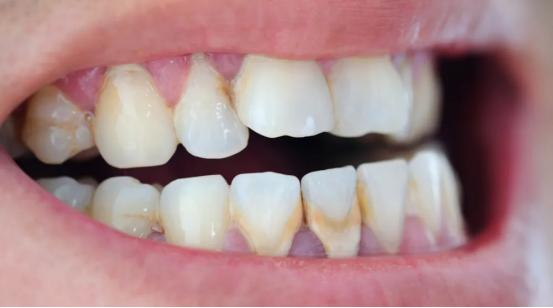

成年后的模样

75%的磷酸钙,15%~25%的水、有机物、磷酸锰、矿酸钙及微量的钾、钠、铁构成,呈黄色、棕色、或者黑色。

0度:无软垢及牙结石。

1度: 少许软垢或牙结石,但未超过牙面的l/3。

2度:有牙结石,未超过冠面的1/3,有少量的龈下结石。

3度:牙结石不超过冠面的2/3,有较多的龈下结石。